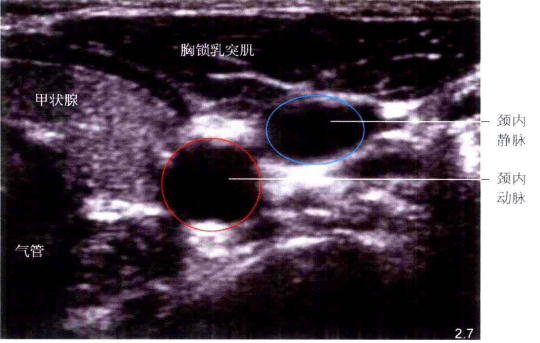

横截面

在颈动脉三角的上端处将探头与颈部垂直放置,即可获得颈内静脉横截面超声图像。颈内静脉呈圆形或椭圆形,加压探头时管径显著缩小甚至闭锁。浅部为胸锁乳突肌,内下方为颈动脉,颈动脉内侧为甲状腺和气管。